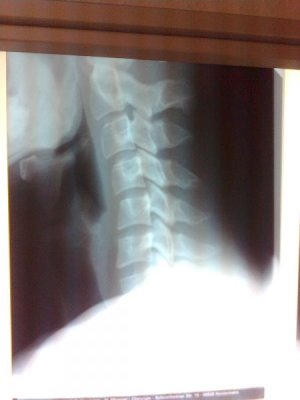

ein kleines Bild vom Unfall - Halswirbelstauchung - uns (Kollege und mir) is n fiat hinten rein geballert vor 2Wochen, war zum Glück nicht der .:R .

Die anderen hab ich gestern schnell gemacht.

Grüße

Anhänge

• Bild0342.jpg

Bild0342.jpg

20 KB · Aufrufe: 116

• Bild0346.jpg

Bild0346.jpg

54,3 KB · Aufrufe: 116

• Bild0349.jpg

Bild0349.jpg

57,1 KB · Aufrufe: 116